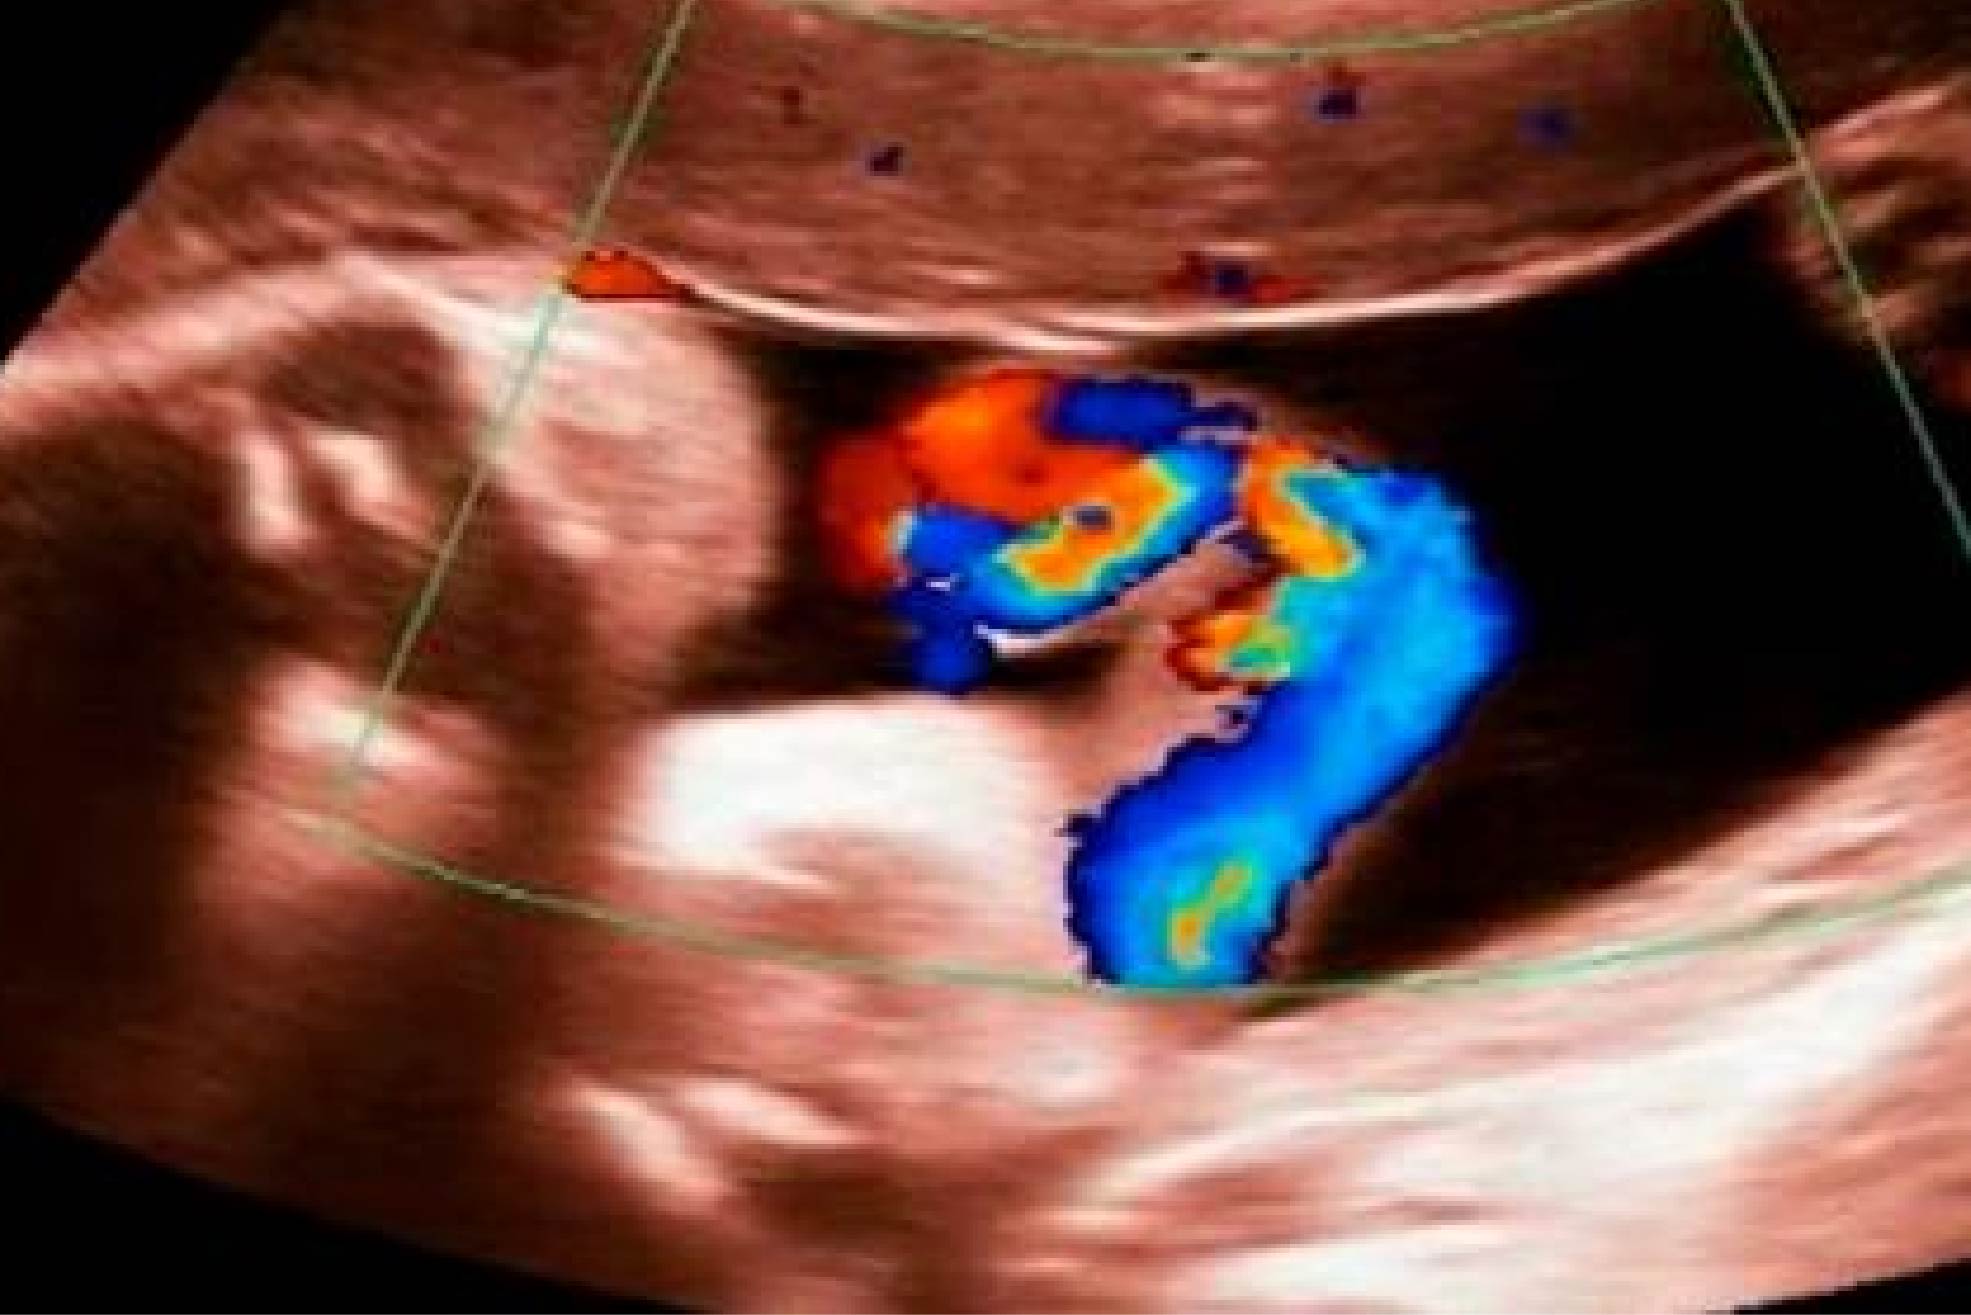

Doppler Fetal

Avalia o fluxo sanguíneo entre a placenta e o bebê, garantindo que ele esteja recebendo oxigênio e nutrientes adequados. Indicado para monitoramento de gestações de alto risco.